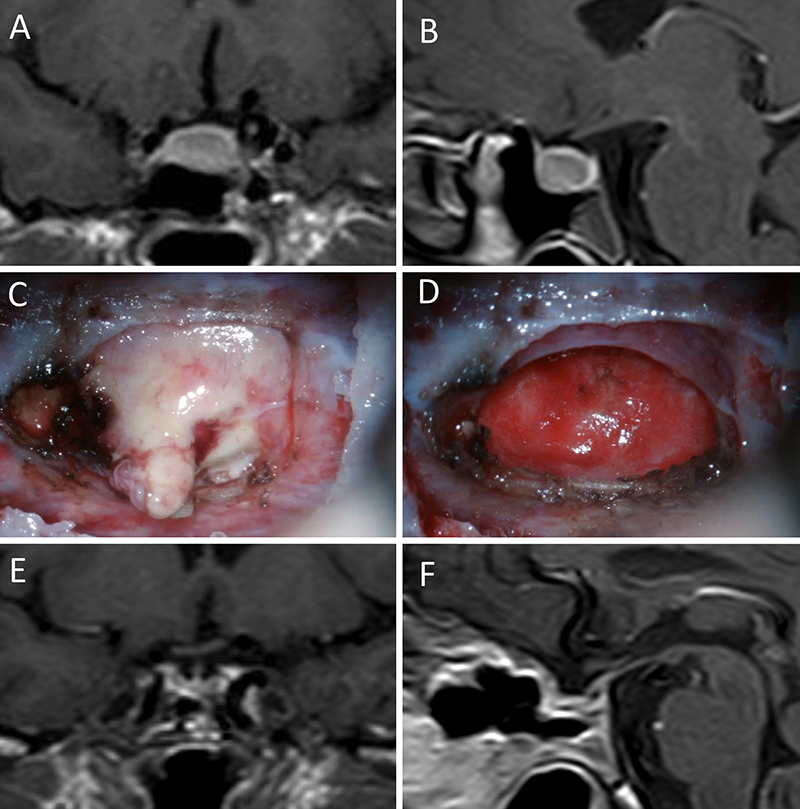

Figura 1: Macroadenoma no funcionante en mujer de 65 año s. Se decidió la cirugía tras evidenciarse crecimiento en los controles. Evolucionó favorablemente desde el punto de vista clínico-radiológico. A-B: RM preoperatoria; C-D: intraoperatorio; E-F: RM postoperatoria.

Figura 2: Macroadenoma no funcionante en mujer de 31 años. La paciente presentó en el preoperatorio déficit visual que mejoró tras la cirugía. A-B: RM preoperatoria; C-D: intraoperatorio; E-F: RM postoperatoria.